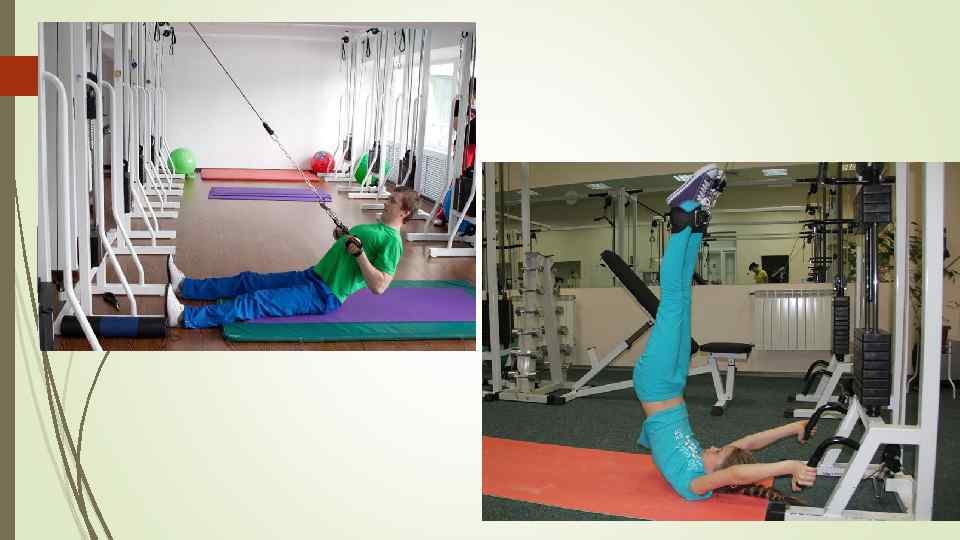

III период 1, 5 -2 месяца после травмы Физическая нагрузка увеличивается, улучшается координация движений и подвижность позвоночника Назначаются У. с сопротивлением, малым отягощением, изометрические напряжения, с большой продолжительностью И. П. - лежа на спине, лежа, упор на колени

IV - период 2 -3 месяца после травмы Особенность: Переход к полной осевой нагрузке на позвоночник Восстановление нормальной подвижности позвоночника Разрешается вставать из положения лежа И. П. - стоя на коленях, возле опоры Рекомендуются У. в воде и плавание К концу 3 месяца больной должен ходить 1, 5 - 2 часа не испытывая боли и дискомфорта. При отсутствии боли в области повреждения разрешается присаживание с подкладыванием валика на область поясничного лордоза.